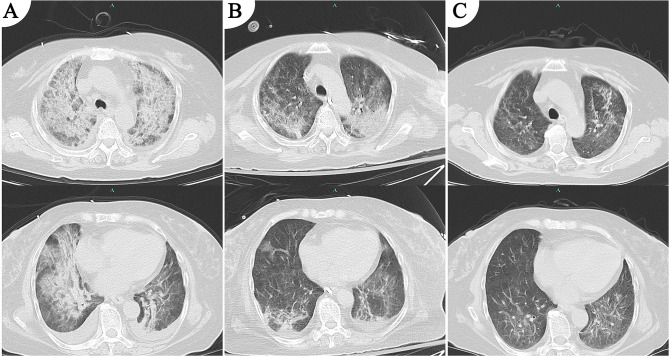

Case presentation: This report describes a case of SCAP-induced sepsis detected six pathogens by mNGS in a patient with IgA nephropathy who developed immunosuppression following long-term treatment with rituximab and corticosteroids. Bronchoalveolar lavage fluid (BALF) mNGS detected six pathogens, including Pneumocystis jirovecii, Klebsiella pneumoniae, Primate bocaparvovirus 1, Cytomegalovirus, Elizabethkingia anophelis, and Candida albicans. The patient was admitted to the intensive care unit (ICU) and received a combination of meropenem, trimethoprim-sulfamethoxazole, ganciclovir, piperacillin-tazobactam, and caspofungin. Following appropriate treatment, the patient recovered and was successfully discharged.